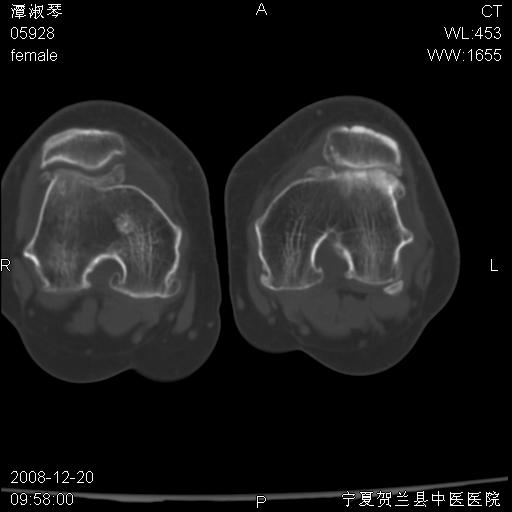

标题: CT17526:请各位看看是啥? [打印本页]

标题: CT17526:请各位看看是啥?

支持骨梗死,退行性骨关节病,膝关节积液.

考虑骨梗死可能性大

骨梗死可能性大

左股骨下段骨梗死。双膝退变。

左胫骨下端松质骨及髓腔内可见点片状高密度灶,骨皮质无明显膨胀及变薄。病变范围较长。支持骨梗死,退行性骨关节病,膝关节积液